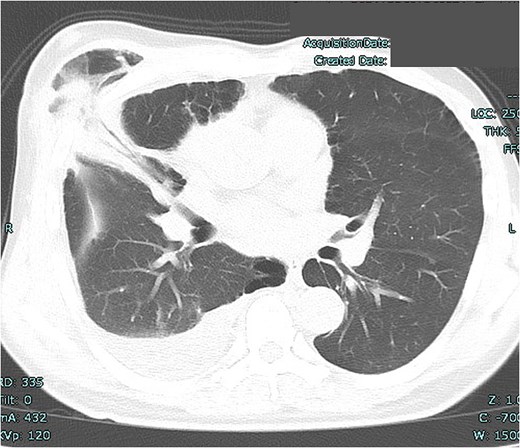

A 53-year-old man underwent mitral valve repair (MVR) via MICS to treat mitral regurgitation. One month postoperatively, the patient presented with swelling of the right anterior chest (Fig. 1). High-resolution computed tomography (HRCT) revealed lung herniation at the fourth intercostal space (ICS), corresponding to the incision site of the previous MICS procedure on the right chest wall (Fig. 2).

Lung herniation of the right middle lobe at the fourth intercostal space.